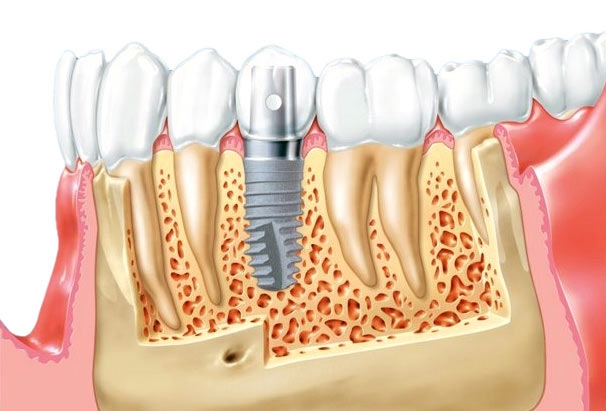

Фото и примеры имплантации зубов при пародонтите

Раздел: Необычные решения